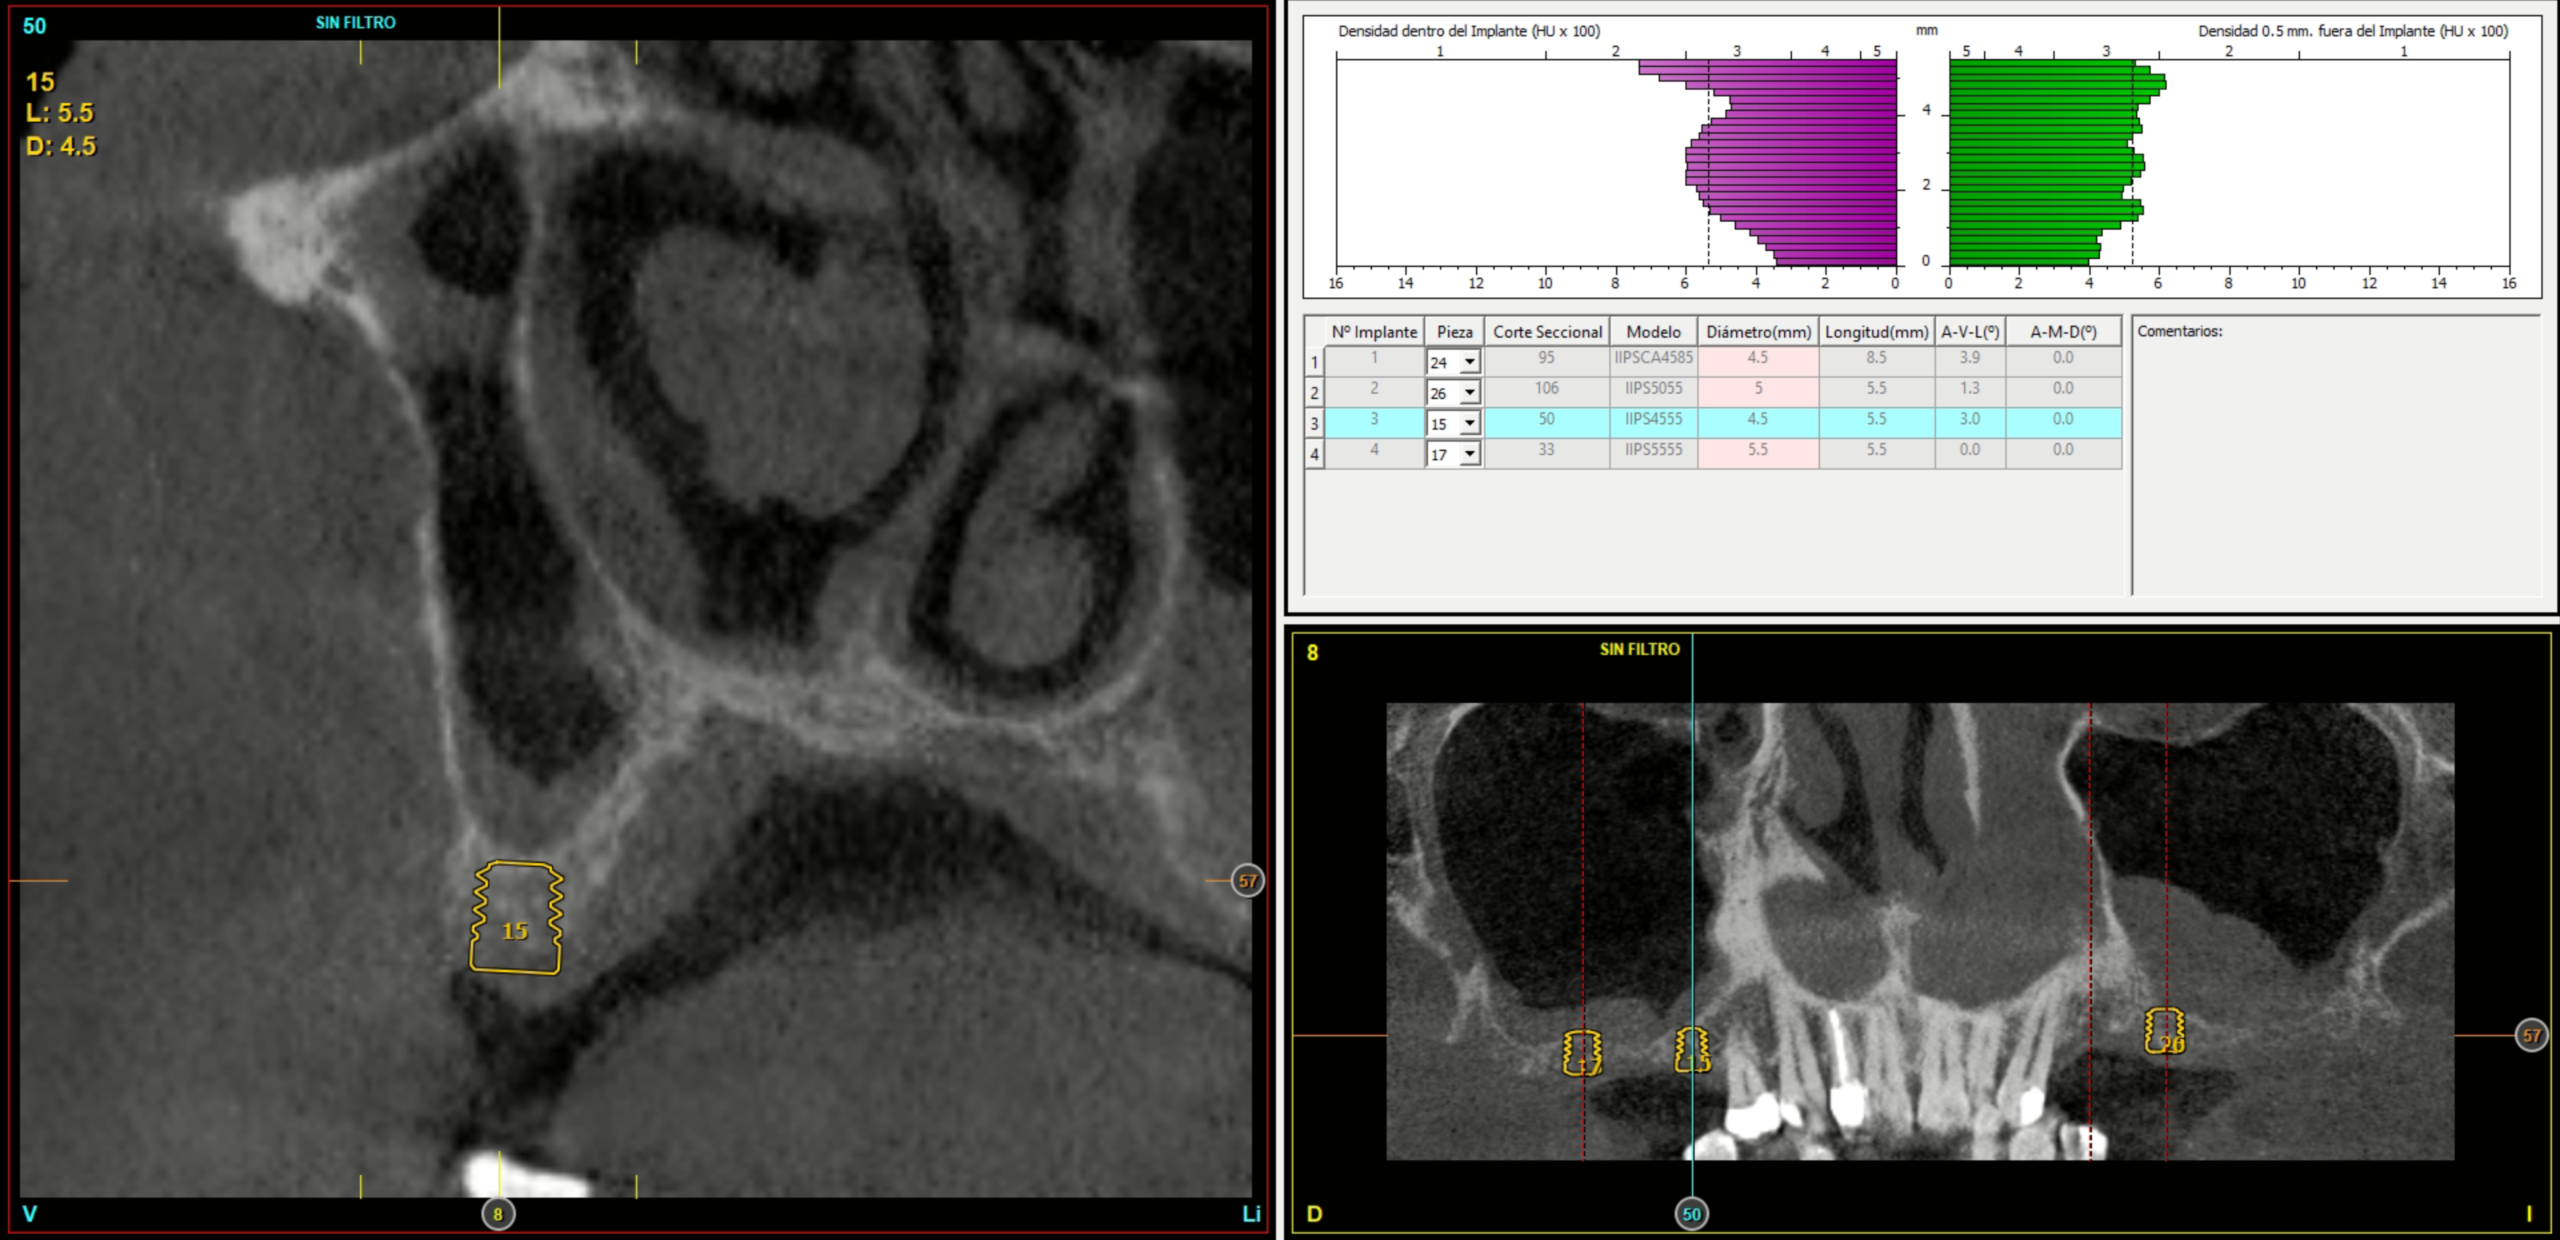

È stata effettuata una revisione retrospettiva di tutti i casi nei quali sono stati inseriti impianti di 4,5 mm di lunghezza sottoposti a protocollo di carico immediato. I trattamenti sono stati eseguiti in un’unica clinica di Vitoria (Spagna) negli anni 2020 e 2021. Nell’ambito dello studio preoperatorio, tutti i pazienti sono stati valutati mediante esame clinico, modelli diagnostici e CBCT (Cone Beam), successivamente analizzati con un software di pianificazione dedicato (BTI-Scan III). Al fine di definire con precisione la futura riabilitazione, è stato eseguito un ceraggio diagnostico dal quale è stata realizzata una guida chirurgica personalizzata.

L’altezza media della cresta ossea residua era di 5,11 ± 1,06 mm, mentre la densità ossea media nelle sedi implantari era di 566,67 ± 349,48 HU. Il torque medio di inserimento degli impianti è stato di 34,71 ± 18,25 Ncm. L’analisi del torque in funzione della posizione implantare e del tipo di osso ha evidenziato un comportamento biomeccanico coerente con la densità ossea attesa per ciascuna regione anatomica. Gli impianti inseriti in osso di tipo I e II hanno generalmente raggiunto valori di torque più elevati, frequentemente compresi tra 40 e 60 Ncm, soprattutto nelle regioni posteriori (26, 27, 36 e 37). Al contrario, negli impianti inseriti in osso di tipo III e IV, i valori di torque tendevano a essere inferiori e più dispersi, oscillando prevalentemente tra 20 e 40 Ncm. Nonostante ciò, anche nei siti con qualità ossea inferiore, i valori ottenuti rientravano in intervalli clinicamente accettabili per consentire la stabilità primaria necessaria ai protocolli di carico immediato adottati nello studio. Nel Grafico 3 è riportata la distribuzione del torque in base alla sede anatomica e al tipo di osso.

Al termine del follow-up, la perdita ossea crestale media è stata di 0,73 ± 0,18 mm in mesiale e di 0,85 ± 0,34 mm in distale. Alcuni casi clinici rappresentativi sono illustrati nelle Figure 2-10.